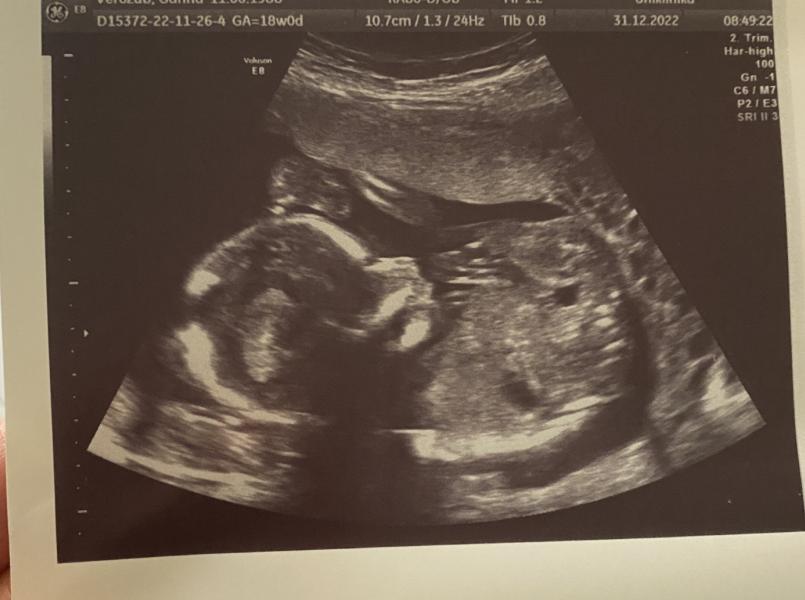

Сьогодні були на другому скринінгу, строк 18 тижнів , буде хлопчик )